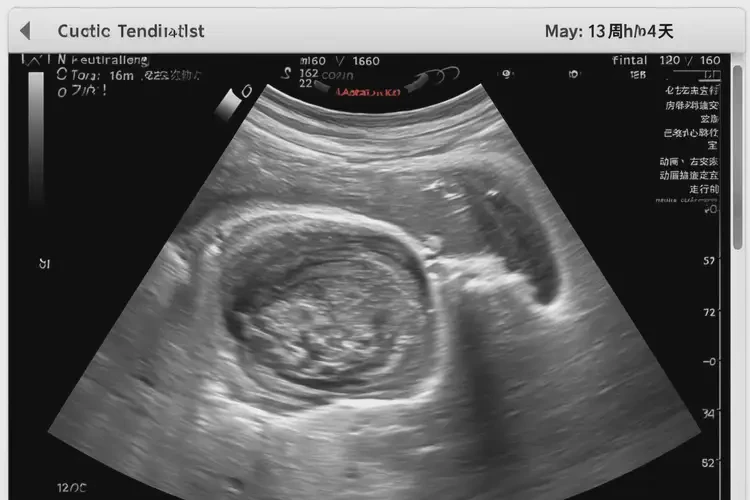

孕13周4天胎心162有危險(xiǎn)嗎

162次/分鐘

孕13周4天的胎心為162次/分鐘,通常在正常范圍內(nèi)。胎兒心率在孕早期較快,隨著孕周增加會(huì)逐漸減慢。以下是關(guān)于胎心的詳細(xì)信息:

孕13周4天胎心162有危險(xiǎn)嗎(圖1)